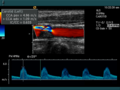

Die Aussagekraft der Sonografie kann erheblich durch die Anwendung des Doppler-Effekts erhöht werden. Man unterscheidet eindimensionale Verfahren (Pulsed-Wave-Doppler, Continuous-Wave-Doppler, auch als D-mode bezeichnet) von zweidimensionalen, farbkodierten Anwendungen (Farbdoppler – F-mode). Die Kombination B-Bild mit Pulsed-Wave-Doppler (PW-Doppler) nennt man auch Duplex.[4]

Doppler-Verfahren werden benutzt zur Bestimmung von Blutfluss-Geschwindigkeiten, zur Entdeckung und Beurteilung von Herz(klappen)fehlern, Verengungen (Stenosen), Verschlüssen oder Kurzschlussverbindungen (Shunts).

Bei der farbkodierten Doppler-Sonografie wird für einen großen Bereich eines konventionellen Ultraschallbildes (Color-Window) die örtliche Doppler-Frequenz (= mittlere Flussgeschwindigkeit) und deren Schwankungsbreite bestimmt. Damit möchte man die Turbulenz der Strömung abschätzen. Aufgrund der statistischen Bewegungen der Streuteilchen ist die Schwankungsbreite der Fließgeschwindigkeit jedoch stets größer als die Turbulenz. Das Ergebnis wird in Falschfarben auf dem B-Bild überlagert, also in Farbtönen von rot und blau für verschiedene Blutgeschwindigkeit und grün für Turbulenz. Hierbei steht üblicherweise die Farbe Rot für Bewegung auf den Schallkopf zu, während mit blauen Farbtönen Flüsse weg von der Sonde codiert werden. Bereiche der Geschwindigkeit 0 werden durch die Elektronik unterdrückt.